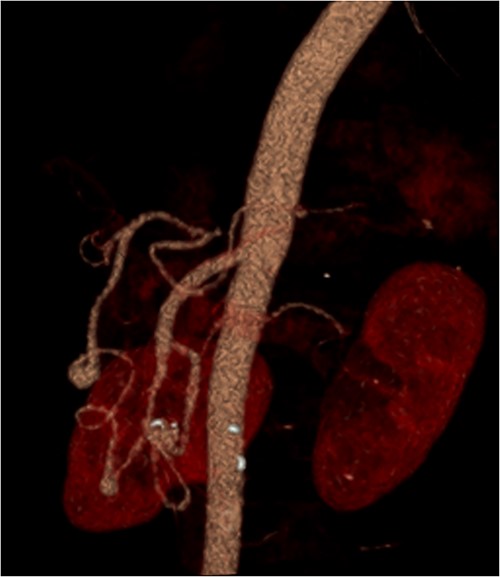

A multiphase CT of the pancreas had unexpected findings. There were no pancreatic masses on the arterial and portal phase study, and no paraaortic or mesenteric lymphadenopathy. The abnormal calcification seen on the previous study corresponded to a dilated vessel along the superior margin of the pancreatic body. This dilated vessel was an abnormal communication between a tortuous ecstatic gastroduodenal artery and the first branch of the SMA, a Buhler’s arc communication. The celiac axis origin was narrowed >90%. No other suspicious solid organ mass lesion was identified. Soft tissues were unremarkable (Figs 5–8).

3D reconstruction demonstrating abnormal communication between the CA and SMA.